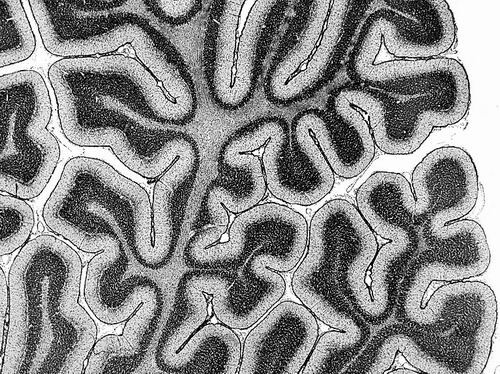

随着人的成长,大脑中协同工作的区域会发生变化。图片来源:Microscape